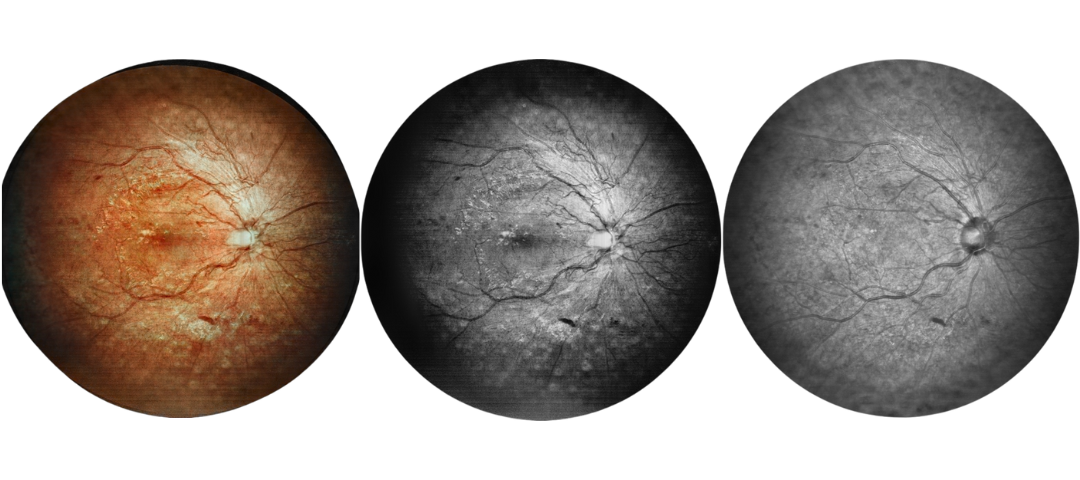

Scanning Laser Ophthalmoscope Obtain Retinal Layer and Choroidal Layer

Our scanning laser ophthalmoscope uses multi-wavelength laser scanning to penetrate the fundus, capture details of the retinal and choroidal layers, and obtain high-definition fundus images.

Fundus Cases Display

Our SLO makes fundus examination easier for you, capturing ultra-clear and wide-angle images of the retina and choroid, and then synthesizing color fundus images to present a rich picture of the fundus status.

Diabetic retinopathy: post photocoagulation

Diabetic retinopathy: bleeding

Diabetic retinopathy: vascular abnormalities, bleeding spots, and post-photocoagulation

Diabetic retinopathy: bleeding, exudation and choroidal vascular abnormalities